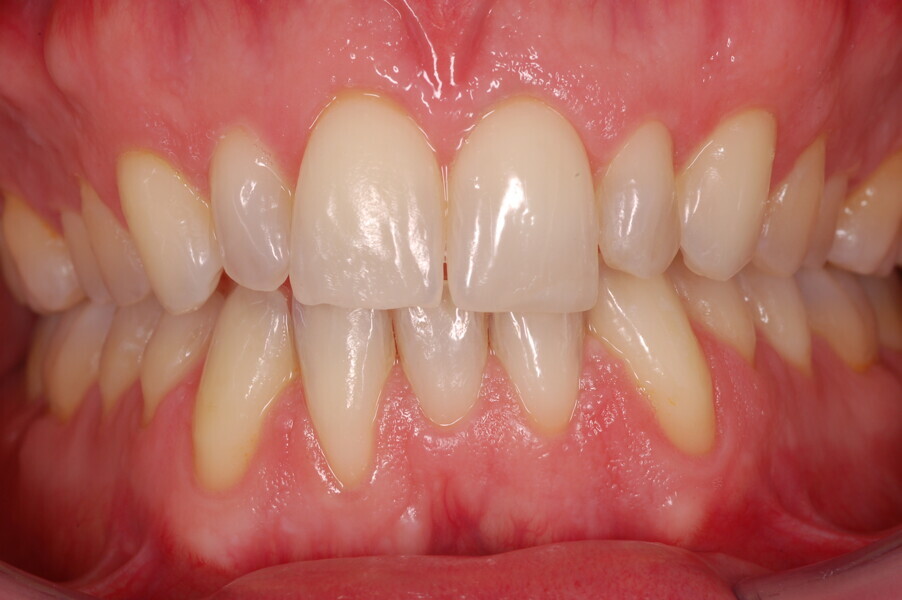

Figs. 1–8: Pretreatment facial and intra-oral photographs.

A healthy 39-year-old man presented to our orthodontic office with the chief complaint of an unattractive dental appearance and fear of the orthognathic surgery proposed by another orthodontist. Clinically, the patient’s profile was straight, and the frontal view did not show any facial asymmetry. The functional examination did not reveal any mandibular deviation or reduced movements. The patient had no joint pain, and no joint noise was observed.

From the periodontal point of view, the patient showed a good attitude to oral hygiene, but crowding of the mandibular incisors made cleaning difficult in that area, causing plaque accumulation and localised gingival inflammation. The panoramic radiograph revealed the presence of the mandibular third molars and confirmed the absence of the mandibular right central incisor (Fig. 10).